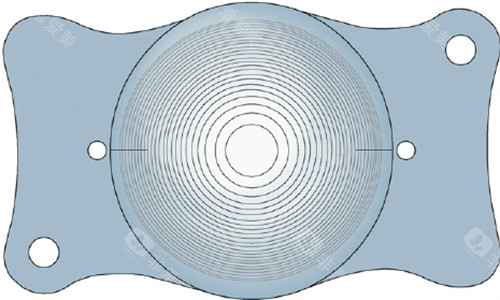

2. 国产晶体:聚焦主流需求,性价比突出

国产晶体则更在意“实用主义”。

以普诺明的散光矫正型晶体为例,其通过优化光学区设计,能有效矫正低中度散光,价格比进口同类产品低;晶安的单焦点晶体则以“基础款”定位,价格亲民,适合预算有限的患者。

近年来,国产晶体也开始布局多焦点领域,如蕾明视康的多焦点晶体,已能实现远、近视力切换,满足日常用眼需求。